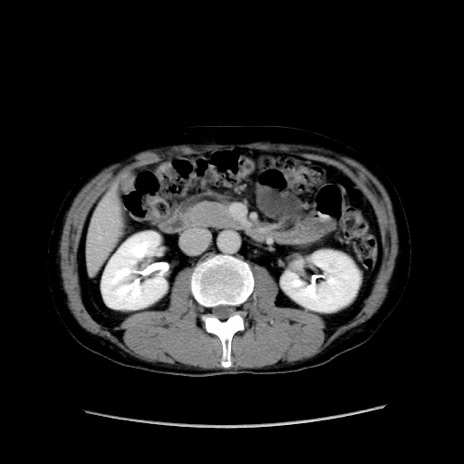

冠状断像

症例37(横断像)

【症例】40歳代 男性

【主訴】腹痛

【現病歴】4時間ほど前に電車に乗車中に臍部上より腹痛出現。徐々に増悪し起立困難となり、救急外来受診。生ものは数日食べていない。今朝お雑煮を食べた。

【身体所見】BT 36.8℃、BP 117/84mmHg、HR 91/min、SpO2 97%、苦悶様、腹部:臍上部広範囲圧痛あり、反跳痛±

【データ】WBC 8100、CRP 0.03